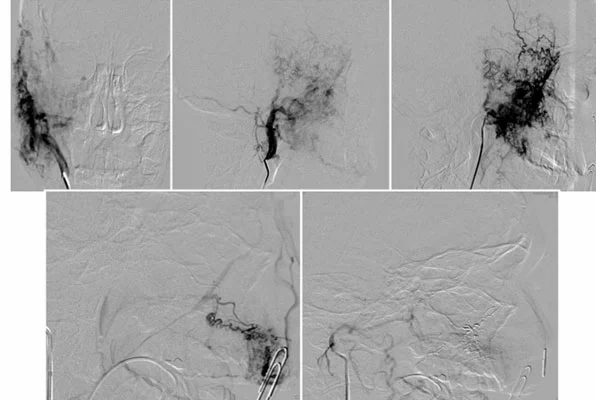

Inoltre, l’embolizzazione transcatetere delle arterie afferenti può essere utilizzata per ridurre il flusso sanguigno verso la malformazione prima dell’intervento chirurgico, limitando le perdite di sangue durante l’operazione.